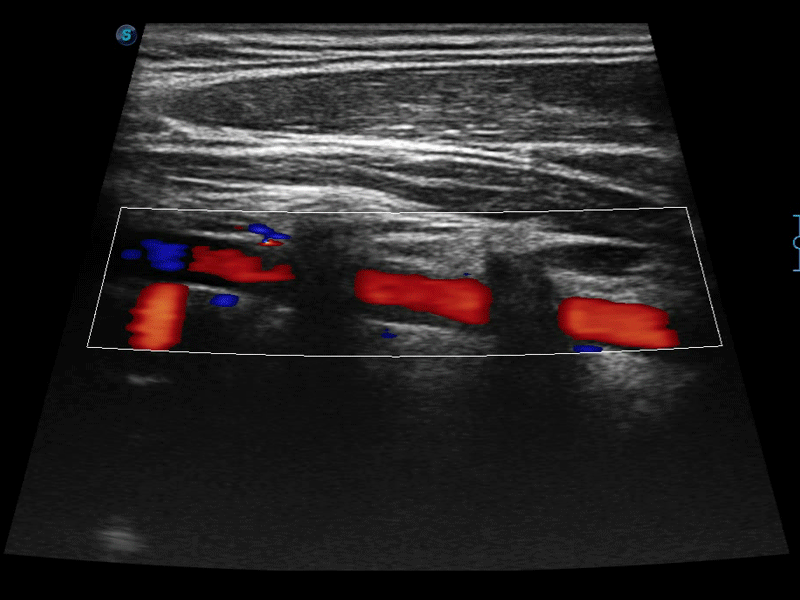

凸陣、線陣和相控陣探頭進(jìn)行實(shí)時(shí)掃描時(shí),開(kāi)啟擴(kuò)展成像模式,可以擴(kuò)展超聲圖像視野,以便更完整地查看大的病灶或組織器官的解剖結(jié)構(gòu)。

通過(guò)色彩血流和實(shí)時(shí)寬景相結(jié)合,可觀察到完整的靜脈或動(dòng)脈的血流,方便醫(yī)生檢查。實(shí)時(shí)掃查過(guò)程中,如有任何操作失誤也可以很容易地進(jìn)行回掃擦除,而不會(huì)中斷掃查。